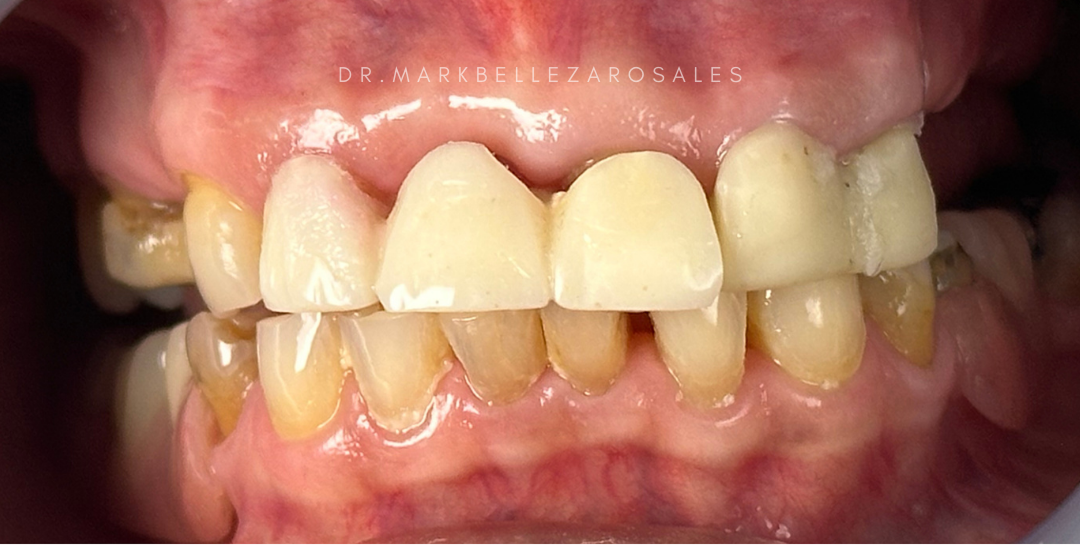

A porcelain fused metal bridge is a fixed dental restoration used to replace missing teeth by combining a strong metal framework with a porcelain exterior. It offers durability and support while maintaining a natural tooth-like appearance for effective chewing and a balanced smile.